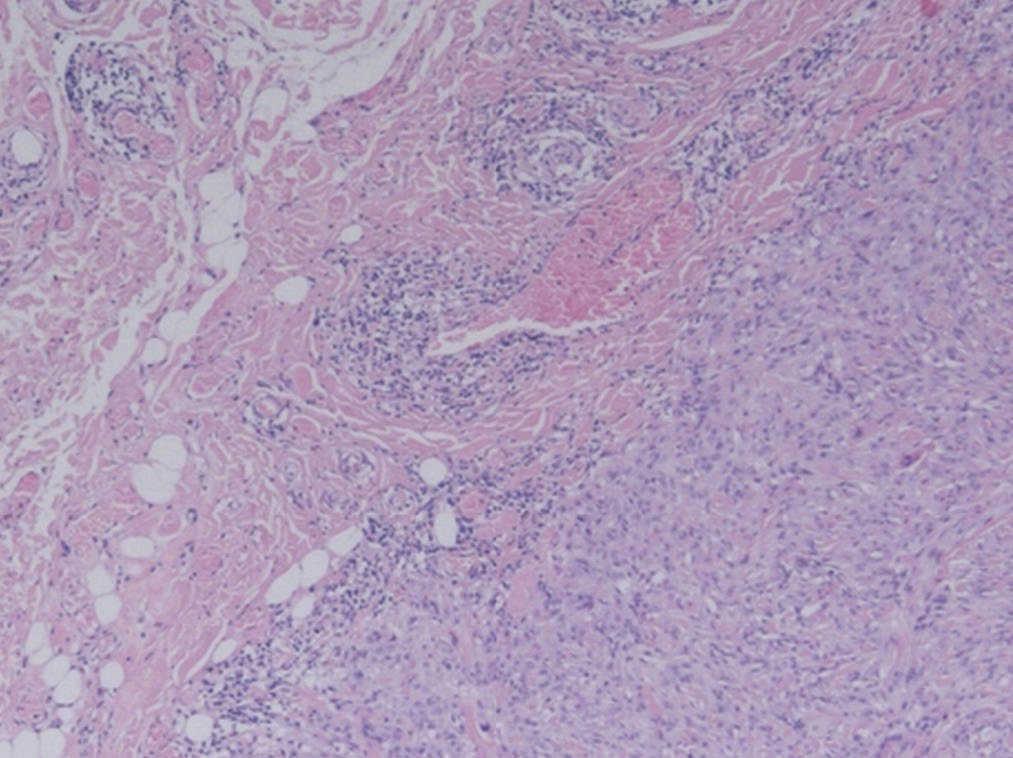

La formación nodular que se envía para estudio anatomopatológico; mide 1,8 x 1,5 cm, es de consistencia firme y coloración amarillenta. Microscópicamente se corresponde con una masa multinodular, localizada en la hipodermis, mal delimitada, que no está encapsulada e infiltra grasa en algunas áreas (fig. 1) Está constituida por células de citoplasma amplio y eosinófilo, con tendencia a formar nódulos con haces gruesos de fibras colágenas. Los núcleos son grandes y redondos u ovalados. Se observan signos de malignidad como atipia, pleomorfismo celular e invasión perineural. Otras zonas muestran un patrón de crecimiento fusiforme y un estroma con cambios mixoides (fig. 2). Con técnicas de inmunohistoquímica, las células tumorales expresan fuerte positividad para vimentina, queratinas AE1/AE3 y EMA, y positividad focal para CD34, actina y citoqueratina 7 (fig. 3). No se observa inmunoexpresión de CK20, CD31 ni S-100. El índice proliferativo (Mib-1) es bajo, del 5%. Con estos datos se establece el diagnóstico de sarcoma epitelioide de tipo proximal de vulva.

Figura 1.En la tinción con hematoxilina-eosina existen criterios de malignidad como la infiltración grasa (HE, x40).